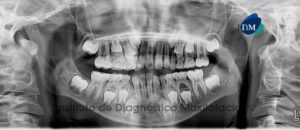

Paciente masculino, 11 años de edad es referido al Instituto de Diagnostico Maxilofacial (IDM) para evaluación general.A la evaluación de la radiografía panorámica (ortopantomografía) se